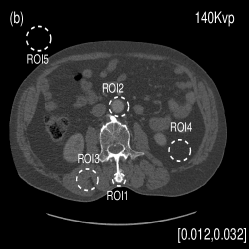

We also evaluated the proposed PWLS-TNV- method using clinical pelvis data. The patient’s pelvis data was acquired by Siemens SOMATOM Definition flash CT scanner using DECT imaging protocol. Table 4 lists acquisition parameters in the pelvis data scan. Fig. 5 shows the high- and low-energy CT images of the pelvis data. Fig.5 (b) shows selected basis materials, bone, iodine, muscle, fat and air, and their assosicated ROIs highlightened in white dashed line circles. We implemented the Direct Inversion method in mendonca2014a and used its results as the initialization for the PWLS-EP-LOOP xue2017statistical and the proposed PWLS-TNV- method. Fig. 6 shows the decomposed material images by the Direct Inversion, the PWLS-EP-LOOP and the PWLS-TNV- method. Table 5 summarizes the means and noise STDs of the decomposed material images by the above three methods. The volume fraction (VF) accuracies are , , and for the Direct Inversion method, the PWLS-EP-LOOP method and the proposed PWLS-TNV-, respectively. Compared with the Direct Inversion and PWLS-EP-LOOP method, the proposed method improves the VF accuracy by and respectively. The proposed PWLS-TNV- method decomposes basis material images more accurately, suppresses noise and decreases crosstalk, while retaining spatial resolution of the decomposed images compared to the other two methods.